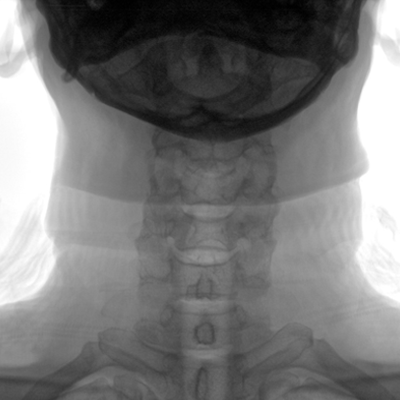

大尺寸動(dòng)態(tài)平板探測器,高DQE、低噪聲、圖像清晰。采用多分辨率圖像增強處理技術(shù),不同部位不同圖像處理算法,滿(mǎn)足客戶(hù)多樣化的需求。

采用智能變頻脈沖透視技術(shù),優(yōu)化圖像質(zhì)量的同時(shí)降低輻射劑量,呵護醫患健康